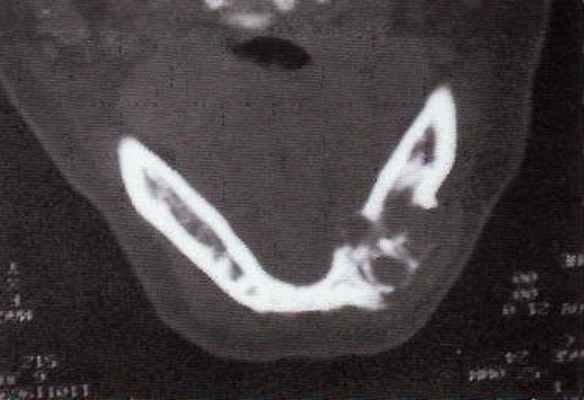

Одонтоамелобластома очень редкая опухоль, состоящая из форм амелобластомы, сочв сочетании с отложениями дентина и эмали, которые иногда напоминают зачаток зуба. Обладает, как и амелобластома, местно деструирующим ростом.

Рентгенологически определяется узловатое плотное образование, окаймленное светлой четкой полосой.

Макроскопически многообразна от небольших образований, напоминающих недоразвитый или деформированный зуб, до массивных конгломератов, состоящих из нескольких зубоподобных образований, легко разделяющихся или плотно спаянных; окружена капсулой. Иногда содержит кисты, заполненные светлой жидкостью.

Фиброма (одонтогенная фиброма)—доброкачественная опухоль из клеточно-волокнистой ткани с тяжами одонтогенного эпителия. Составляет около 3% всех одонтогенных опухолей. Встречается чаще у детей, локализуется обычно в нижней челюсти.

Рентгенологически — прозрачная тень с четкими границами, на фоне которой можно видеть включения зубных конгломератов; местами отмечается разрушение кортикальной пластинки.